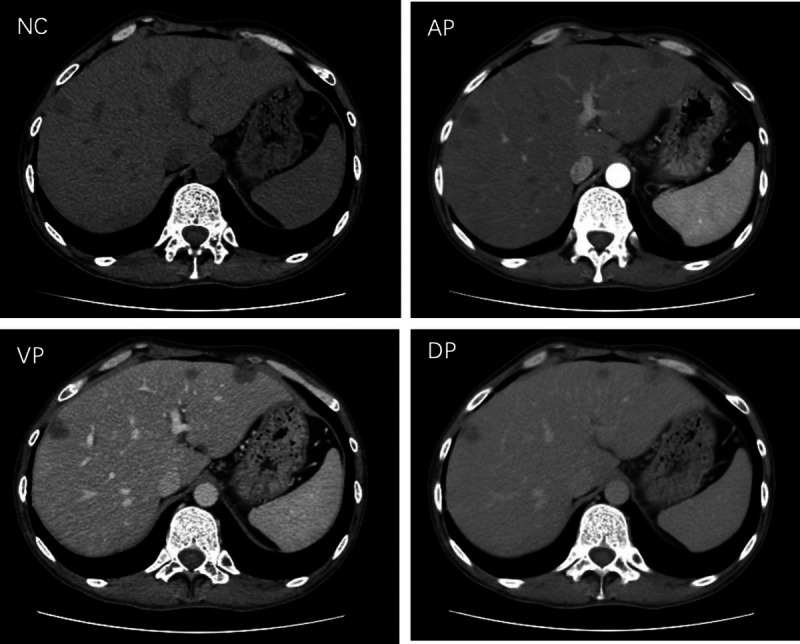

Abstract Image